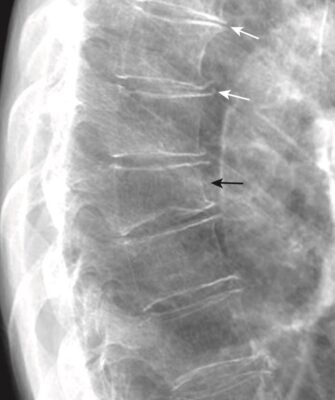

Cột sống ngực

- Thông thường, các thân đốt sống ngực có hình dạng gần giống hình chữ nhật và mỗi bản tận của thân đốt sống song song với bản tận của thân đốt sống ở trên và dưới nó. Mỗi khe đĩa đệm cao hơn một chút hoặc giữ nguyên như khe bên trên nó trong suốt cột sống ngực.

- Thoái hóa đĩa đệm có thể dẫn đến hẹp khe đĩa đệm và hình thành các gai xương nhỏ ở rìa của các thân đốt sống.

- Khi bị gãy do nén ép, thường là do loãng xương, thân đốt sống mất chiều cao. Gãy xương do nén thường làm bản tận trên của thân đốt sống lõm xuống (Hình 9).

- Đừng quên quan sát cột sống ngực khi đánh giá X quang phổi nghiêng để tìm các dấu hiệu có giá trị về các bệnh lý hệ thống.